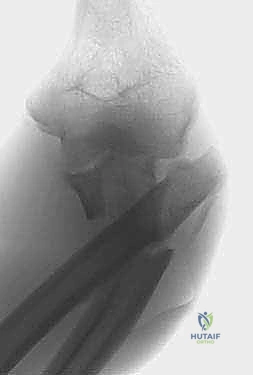

FIG 1 • Plain AP radiograph typically demonstrates fracture pattern.

FIG 1 • Plain lateral radiograph typically demonstrates fracture pattern.

FIG 1 • Plain oblique radiograph typically demonstrates fracture pattern.